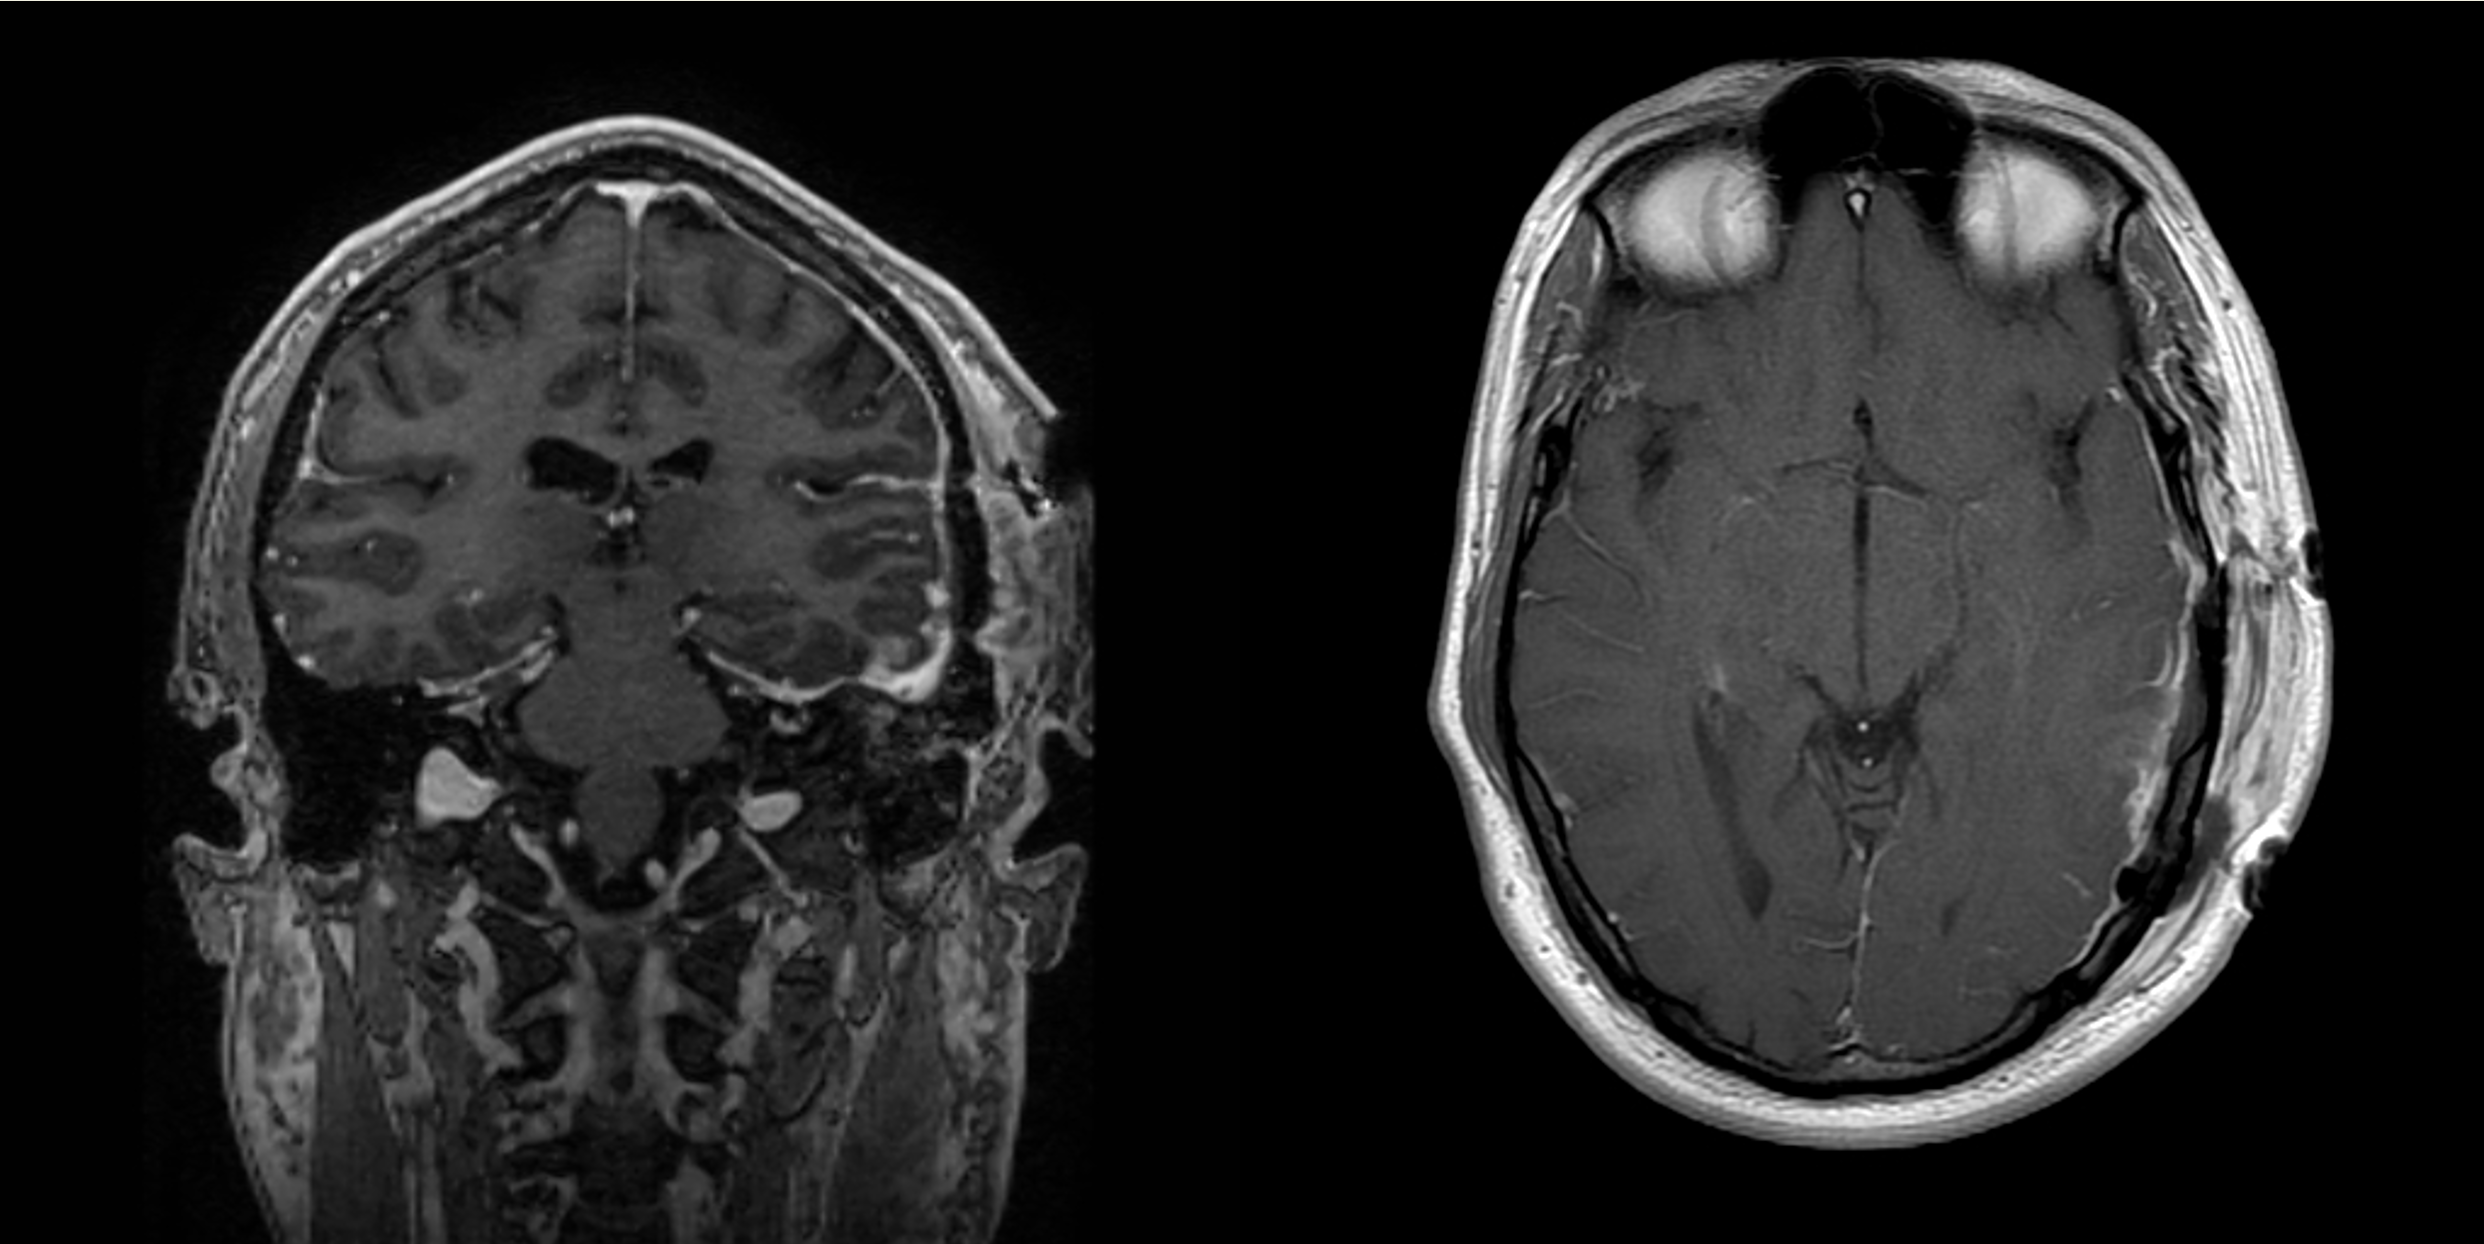

Fig. 1 Myelin Water Imaging of two selected patients

Screenshot 2025 06 01 at 12.05.23 pm

Background

This study explored whether Myelin Water Imaging could detect myelin injury in Anti-NMDA receptor autoimmune encephalitis (NMDAr-AIE), where traditional neuroimaging is often normal. Myelin Water Fraction (MWF) quantifies myelin content by distinguishing myelin sheath water from other brain water compartments.

Methods

Adult participants with confirmed NMDAr-AIE diagnoses and healthy controls (HC) underwent 3T brain MRI (Magnetic Resonance Imaging) including MWF mapping. Participants were recruited after discharge from the hospital. Mean MWF was calculated for 4 white matter regions of interest (ROI). MHI (Myelin heterogeneity Index) was calculated by dividing the MWF standard deviation by the mean MWF. Patient demographics, clinical assessments, treatment, and outcomes were collected.

Results

Five participants with NMDAr-AIE (4F/1M, mean age 30, SD 7) and four HC (3F/1M, mean age 36, SD 6) were included. All NMDAr-AIE participants had normal or non-specific T2 hyperintensities on initial imaging and had received immunotherapy. The mean Modified Rankin Score (MRS) on discharge was 2. MWF (mean ± SD) for normal-appearing white matter, corpus callosum, corticospinal tract, and superior longitudinal fasciculus were 0.10±0.02, 0.12±0.02, 0.15±0.03, 0.12±0.02, which were very similar to HC at 0.09±0.02, 0.11±0.01, 0.15±0.02, and 0.11±0.02, respectively.

Conclusions and Future Direction

Myelin Water Imaging showed no myelin pathology in five NMDAr-AIE patients, with MWF and MHI values comparable to HC, suggesting that myelin pathways are relatively preserved post-recovery from AIE. Moving forward, we aim to continue recruiting healthy controls, patients post-recovery and those experiencing active disease to determine if there are any MWF abnormalities throughout the disease course. Future studies are needed to assess MWF changes in other antibody-mediated encephalitides.